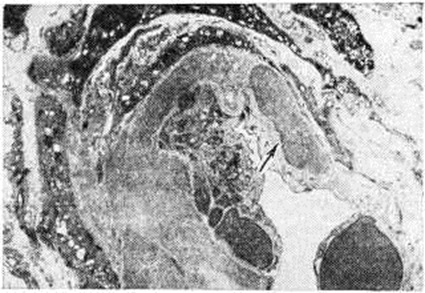

Рис. 1.

Электронограмма приносящего сосуда почечного клубочка при доброкачественной форме нефросклероза: скопление гиалиновых масс под эндотелием (указано стрелкой); × 6000.